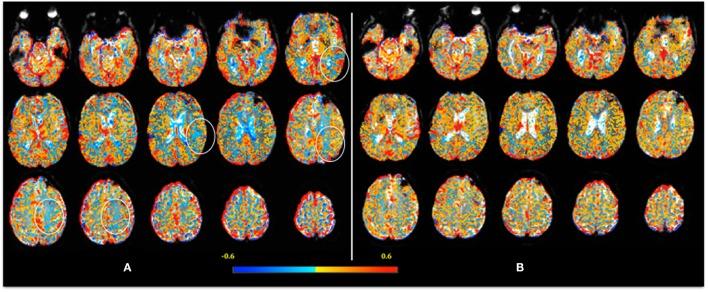

Traumatic brain injury participants were 72% males, mean age being 42.7 years. Control participants were 61% with mean age of 38.7 years. SCAT2 scores tended to improve among those mTBI patients with follow-up visits (p = 0.07); however, they did not tend to recover to scores of the healthy controls. Brain volumes were not statistically different between groups at the first visit (WM p = 0.71; GM p = 0.36). In mTBI patients, there was a reduction in GM volume between visits 1 and 2 (p = 0.0046). Although mean CVR indexes were similar (WM p = 0.27; GM p = 0.36; and WB p = 0.35), the correlation between SCAT2 and CVR was negative in controls (WM-r = -0.59; p = 0.010; GM-r = -0.56; p = 0.016; brain-r = -0.58; p = 0.012) and weaker and positive in mTBI (brain-r = 0.4; p = 0.046; GM-r = 0.4; p = 0.048). SCAT2 correlated with GM volume (r = 0.5215, p = 0.0075) in mTBI but not in controls (r = 0.2945, p = 0.2355).

There is a correlation between lower GM CVR indexes and lower performance on SCAT2 in patients with mTBI, which seems to be associated with more symptoms. This correlation seems to persist well beyond 120 days. mTBI may lead to a decrease in GM volume in these patients.

创伤性脑损伤参与者中男性占72%,平均年龄为42.7岁。对照参与者中男性占61%,平均年龄为38.7岁。在接受随访的mTBI患者中,SCAT2评分有改善趋势(p = 0.07);然而,他们的评分并未恢复到健康对照的水平。首次访视时两组之间的脑容量无统计学差异(WM p = 0.71;GM p = 0.36)。在mTBI患者中,第1次和第2次访视之间GM体积减少(p = 0.0046)。尽管平均CVR指数相似(WM p = 0.27;GM p = 0.36;WB p = 0.35),但在对照组中SCAT2与CVR呈负相关(WM - r = -0.59;p = 0.010;GM - r = -0.56;p = 0.016;全脑 - r = -0.58;p = 0.012),而在mTBI患者中相关性较弱且为正相关(全脑 - r = 0.4;p = 0.046;GM - r = 0.4;p = 0.048)。在mTBI患者中SCAT2与GM体积相关(r = 0.5215,p = 0.0075),而在对照组中不相关(r = 0.2945,p = 0.2355)。

mTBI患者中较低的GM CVR指数与SCAT2较低的表现之间存在相关性,这似乎与更多症状相关。这种相关性似乎在120天之后仍持续存在。mTBI可能导致这些患者的GM体积减少。